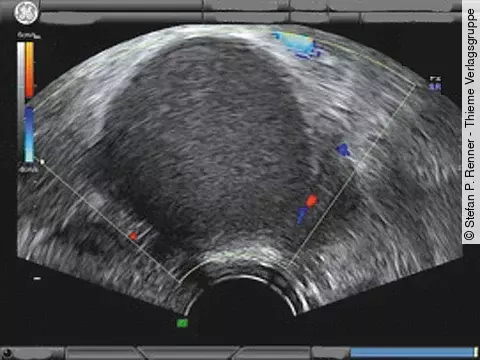

Quiz der WocheWas entdecken Sie im Farb-Doppler?

Sie führen routinemäßig einen Ultraschall bei dieser Schwangeren in der 28. SSW durch. Dabei entdecken Sie folgendes (Bildergalerie): Sie haben daraufhin einen bestimmten Verdacht.